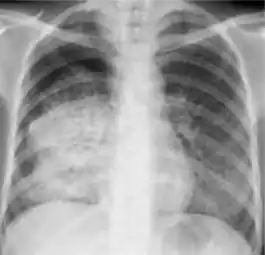

4. Pleural effusion - Presence of a significant amount of fluid within the pleural space. This finding must be distinguished from blunting of the costophrenic angle, which may or may not represent a small amount of fluid within the pleural space (except in children when even minor blunting must be considered a finding that can suggest active TB).

Chest x-ray showing dense opacity pleural effusion in the lower left lung of primary pulmonary TB.